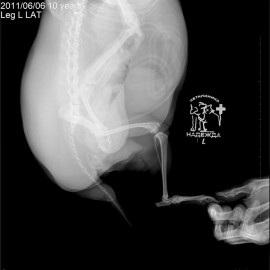

Обратились с жалобами на хромоту на левую тазовую конечность. У собаки отмечается избыточный вес. В клинике был проведен осмотр и рентгенологическое исследование, в ходе которого был поставлен диагноз - разрыв передней крестообразной связки левого коленного сустава. Была проведена операция: TPLO.

Снимок 1 до операции